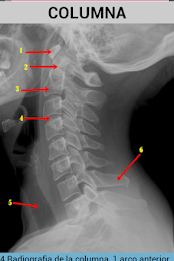

Tato aplikace se naučí snadno identifikovat anatomické struktury, které lze vidět v radiologii.obsahuje obrázky prostých rentgenových snímků, MRI a CT skenů.

Také s každým obrázkem je vysvětlení, které lépe porozumí.

obsahuje obrázky hlavy, páteře a hrudníku.